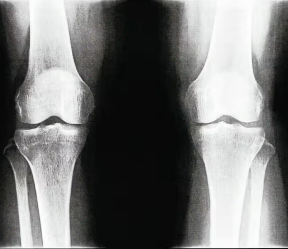

The ABCs of ACL, LCL, MCL, and PCL Knee Injuries

The knee joint is part of a complex cable-pulley system that is foundational for movement. The knee ligaments are “elasticized bands” of tissue that connects the thighbone to the two shin bones that give your knee joint its...

How Some Sports Injuries Can Cause Arthritis at an Early Age

Your high school soccer career ended with a torn anterior cruciate ligament (ACL) and knee surgery. Now, 20 years later, you’re experiencing increasing pain in that same knee and the doctor diagnoses the problem as post-traumatic osteoarthritis (PTOA)...